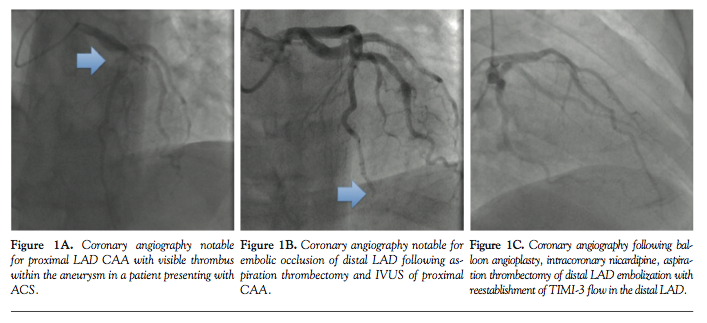

Case 1. A 38-year-old Caucasian male with past medical history of dyslipidemia, obesity, and obstructive sleep apnea presented to the emergency department with an ACS. Initial electrocardiogram demonstrated normal sinus rhythm with 1.0 mm ST-segment depressions in leads III and aVF. Medical treatment was started including intravenous (IV) heparin, clopidogrel 600 mg, aspirin 325 mg, and atorvastatin 80 mg. On coronary angiography, the left anterior descending (LAD) coronary artery had a large aneurysmal segment in the mid-portion of the vessel immediately distal to a moderate to

severe stenosis that was difficult to delineate angiographically (Figure 1A). There was TIMI-2 flow in the LAD. The right and left circumflex coronary arteries also contained aneurysmal sections bordered by regions of non-obstructive CAD. Intravascular ultrasound (IVUS; Boston Scientific) was performed, revealing non-critical proximal LAD stenosis and ~8 mm aneurysmal diameter with visible thrombus. Following removal of the coronary guidewire, angiography revealed abrupt total occlusion of the distal LAD, consistent with distal embolization of thrombus (Figure 1B). A BMW coronary guidewire (Abbott Vascular) was advanced across the thrombus; flow was reestablished following manual thrombectomy, administration of intracoronary nicardipine, and serial low-pressure (<6 atm) Apex 2.5 x 15 mm PTCA balloon inflations (Boston Scientific). Final angiography demonstrated a patent LAD with TIMI-3 flow (Figure 1C). The patient was treated with aspirin, clopidogrel, IV unfractionated heparin and IV abciximab (48 hours). Troponin I (reference, <0.05 µg/L) peaked at 10.2 µg/L. The patient remained asymptomatic during the remainder of the hospital course. He was discharged to home on daily aspirin, clopidogrel, metoprolol, and atorvastatin and has done well throughout follow-up.